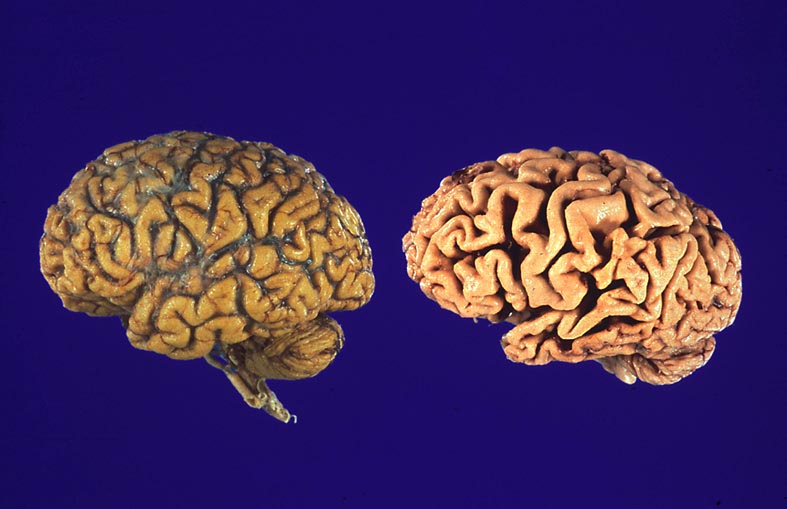

Gehirne von Alzheimer Patienten sind makroskopisch durch eine kortikale Atrophie (vor allem temporo-parietal) charakterisiert. Weiter findet sich meist eine deutliche Atrophie von Hippocampi und Mandelkernen. Diese geht einher mit einem Hydrocephalus internus (e vacuo), wobei vor allem die Temporalhörner der Seitenventrikel betroffen sind.

Makroskopie

Befund

Pathologischer Befund

Normalbefund